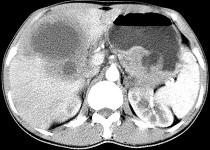

问题 女,61岁,上腹部疼痛一个月,食欲减退,消瘦,CT所见如图,最可能的诊断是 ( )

选项 A.肝脓肿 B.肝转移瘤 C.胃癌肝转移 D.肝包虫病 E.原发性肝癌

答案 C